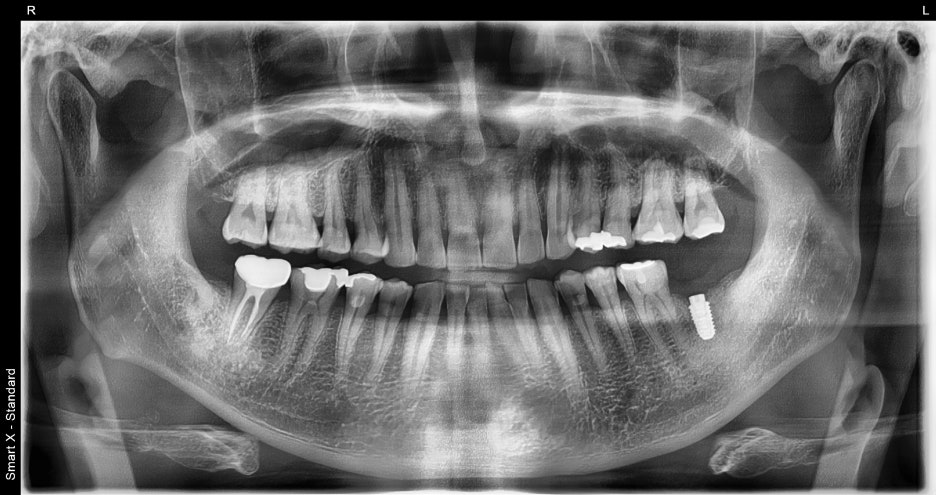

파노라마 엑스레이 촬영 결과,

왼쪽 아래 어금니가 이미 발치된 상태로

주변 뼈 상태는 양호하여

추가 뼈이식 없이 임플란트 식립 가능으로 확인되었습니다.